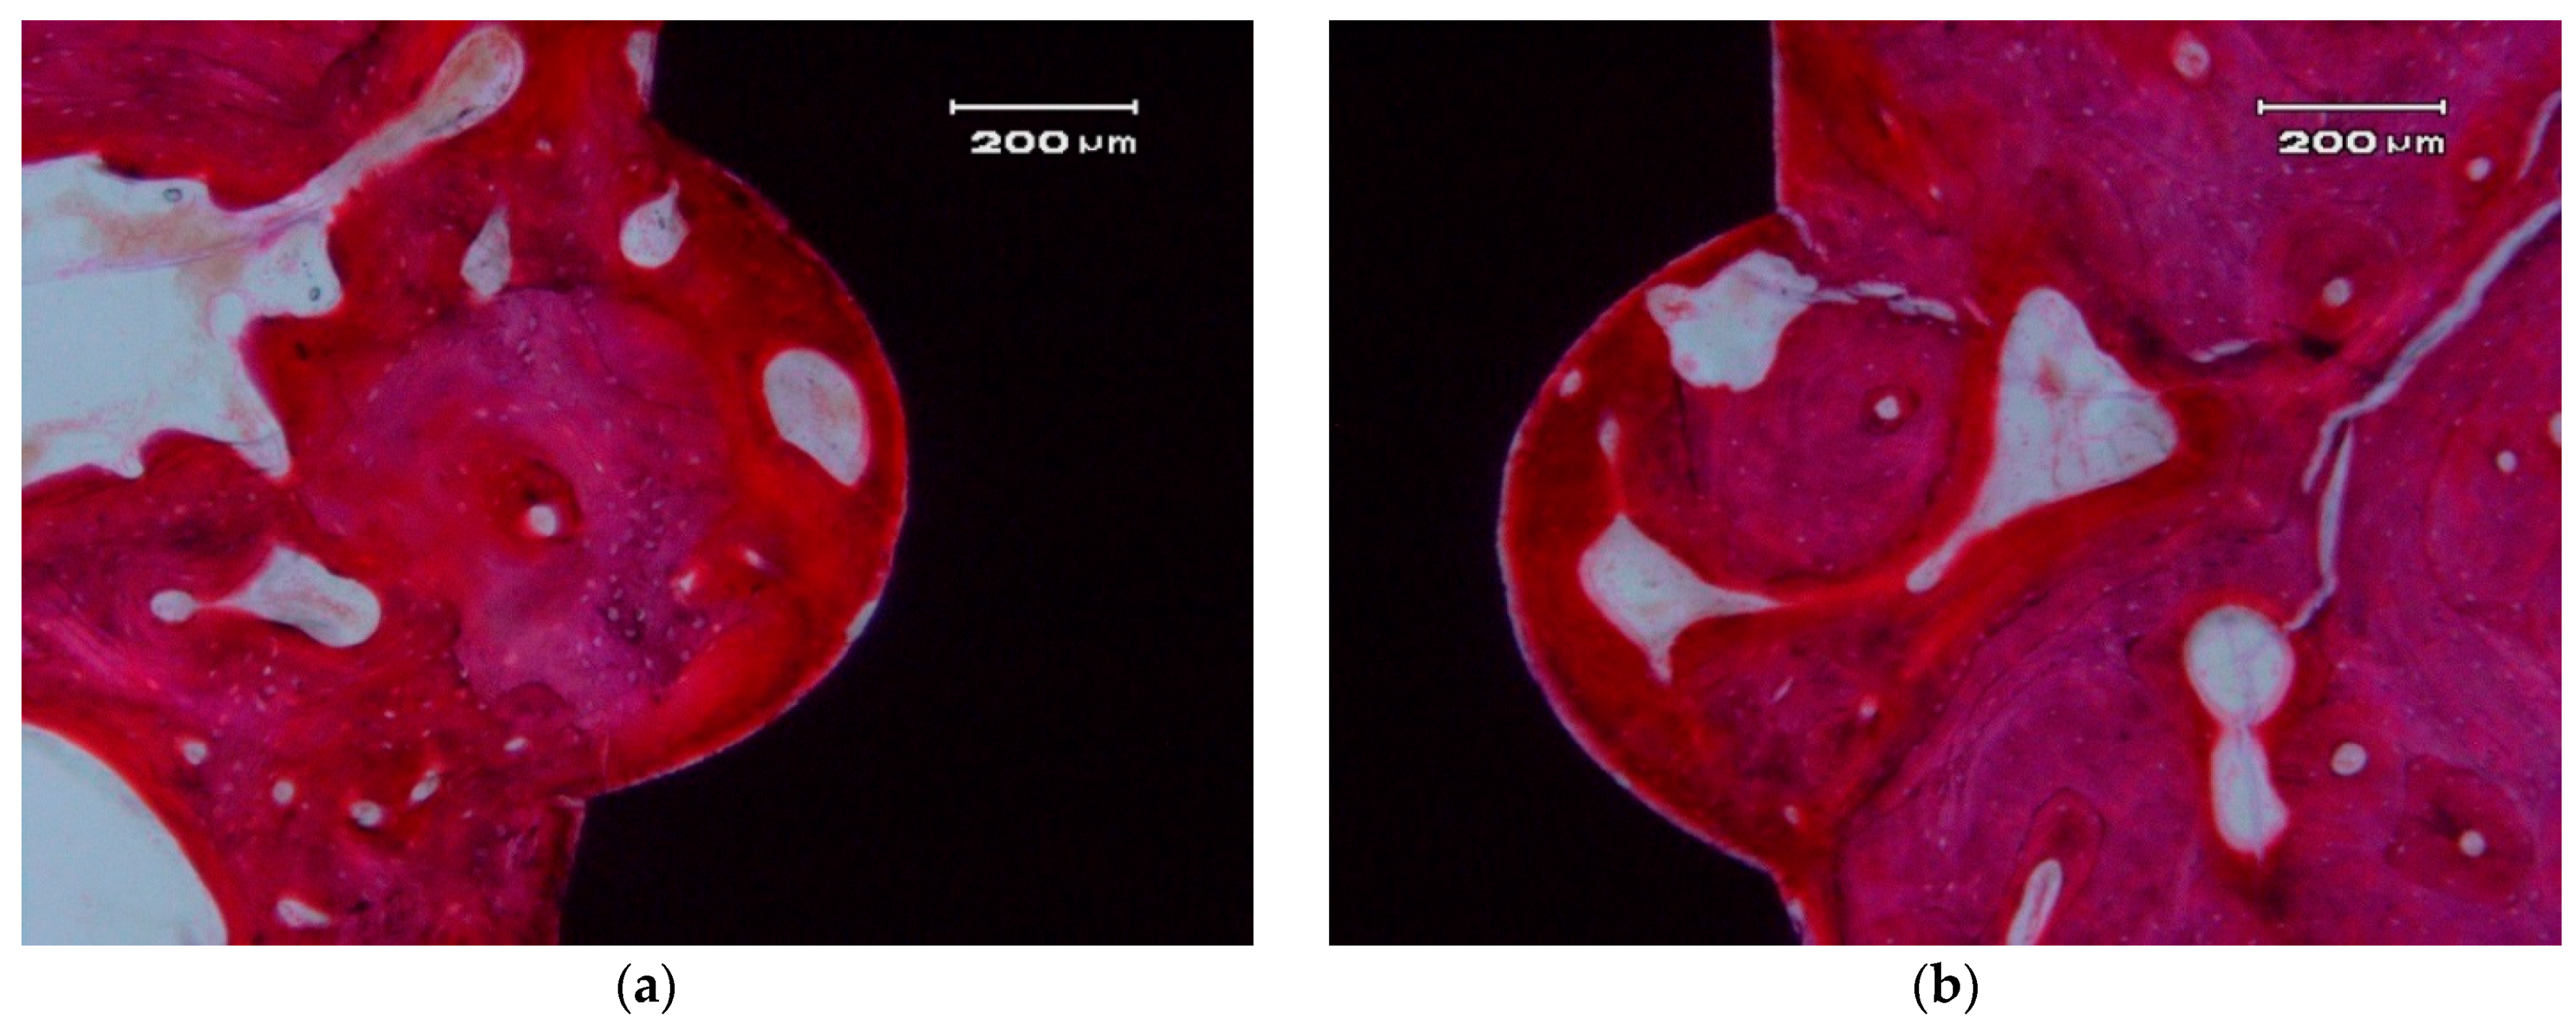

ZCe-A nanocomposite implants showed high bone-to-implant contact (BIC) values (80 ± 5% after eight weeks) (Figure 8). These values are similar to those found by Saulacic et al. [32] for commercially-pure titanium implants (85% BIC) and titanium-zirconia implants (72% BIC), and quite a lot higher than those reported for Ti64 implants (30% BIC). In another recent study performed in miniature pigs [33], mean BIC values of zirconia implants differ depending on the surface modification method applied: sand-blasting (30% BIC), sand-blasting and acid-etching (48% BIC), and sand-blasting and alkaline-etching (22% BIC). Despite the different animal models used, these zirconia implant BIC values are significantly inferior to the osseous integration rate achieved by the ZCe-A nanocomposite, as shown in Figure 8 in posterior maxillary bone. Furthermore, we have not found multinucleated giant cells (MNGCs) along the implant surface in accordance with data found for cpTi implants (0% MNGCs) and in contrast with data found for TiZr implants (3% MNGCs), Ti64 implants (50% MNGCs), sand-blasted Zr implants (17% MNGCs), sand-blasted and acid-etched Zr implants (38% MNGCs), and sand-blasted and alkaline-etched Zr implants (41% MNGCs).

Figure 8.

Osseo-integrated ZCe-A nanocomposite implant after eight weeks of implantation in the posterior maxilla of a Beagle dog at different magnifications. (a) scale bar 2 mm and (b) scale bar 800 µm.